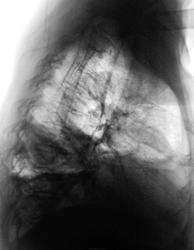

Контроль после лечения в Х.О.

1.dscn0287.jpg2.dscn0287a.jpg3.dscn0288.jpg4.dscn0288a.jpg

Эффект дренирования неоспорим, но - полость сохраняется, и самое главное - а что в пунктате?...неужели - соломенно-желтая?))))

В пунктате - гной